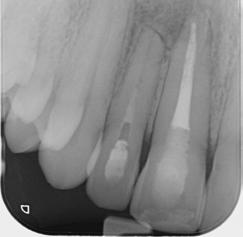

Endodontic treatment of tooth 12 continued with long term calcium hydroxide until the 12’s root canal was eventually filled with GP cones and Ah-26 cement 6 months later.

Radiograph 2 Radiograph 3 Radiograph 4

5. Root filling session tooth 12 (30/01/2024)

6. Immediately after root filling tooth 12 (30/01/2024)